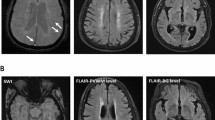

Mixture model parameters correlations with hippocampal volumes. a | Correlation between Filtering rate at Maintenance and whole hippocampal volume (WHV). b |Correlation between Mixture Model metrics and whole hippocampal volume. On the X-axis the volume in mm3 of the whole hippocampus. In b, the Y-axis represent from left to right respectively MAE in degrees, probabilities of Target detection, Misbinding and random Guessing.

Filtering and MAE stratified by WHV and diagnosis. FM on the X-axis, MAE on the Y-axis, hippocampal volumes (WHV) on the Z-axis. Subjects with higher WHV (top of the image) have lower MAE (back of the image), lower Filtering rate at Maintenance scores (on the left) and are predominantly represented by elderly healthy subjects (in coral red), and PD patients (in violet). On the other end of the spectrum, AD patients (in green) have higher Filtering rate at Maintenance scores (on the right), higher MAE (front of the image), and have lower hippocampal volumes (bottom of the image).

Relationship between hippocampal volumes and filtering ability

Across groups, Filtering at Maintenance was significantly negatively correlated with whole hippocampal volume (WHV) (df = 55, r = − 0.404 p = 0.002), (Figs. 5a and 6). Figure 6 displays the relationship between Filtering rate at Maintenance and hippocampal volumes, with participants with higher Filtering rate at Maintenance (on the right side), having lower hippocampal volumes (bottom of the graph). There was no significant correlation between hippocampal volume measures with Filtering rate at Encoding (df = 60, r = − 0.155, p = 0.228) or with Set Size, either at Encoding (df = 61, r = − 0.113 p = 0.379) or Maintenance (df = 60, r = − 0.117 p = 0.365). To further validate this result, we looked at whether Filtering rate at Maintenance was correlated with whole brain volume, and there was no such correlation (df = 55, r = − 0.116, p = 0.392).

Relationship between hippocampal volume and other WM performance metrics

WHV was negatively correlated with MAE (df = 57, WHV: r = − 0.473, p < 0.001), Misbinding (df = 48, WHV: r = − 0.476, p < 0.001) and Guessing (df = 50, WHV: r = − 0.578, p < 0.001) and positively correlated with Target detection (df = 57, WHV: r = 0.474, p < 0.001), (Figs. 5b and 6 for MAE). Figure 6 shows how higher MAE is negatively correlated with hippocampal volumes, as the regression plane goes from higher hippocampal values (top if the image) to lower values (bottom) with increasing MAE values (from back to front of the image on the Y-axis). No association between hippocampal volume and Precision was found (df = 43, WHV: r = −0.057, p = 0.710). In this case, both MAE (df = 57, r = − 0.319, p = 0.014), Target detection (df = 57, r = 0.310, p = 0.017) and Guessing (df = 50, r = −0.335, p = 0.015) were correlated with whole brain volume, while Misbinding was not (df = 48, r = −0.101, p = 0.487).